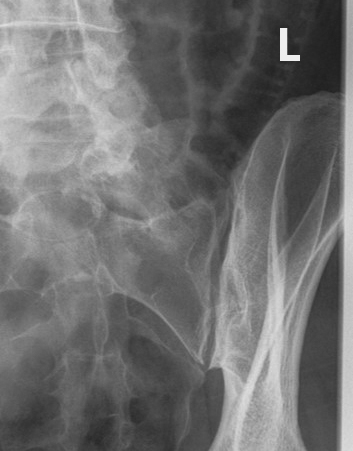

Flashcards covering radiographic projections for pelvic fractures (inlet/outlet views), acetabular fractures (Judet views), and sacroiliac (SI) joints, including patient positioning, CR angulation, anatomical demonstration, and common positioning errors.